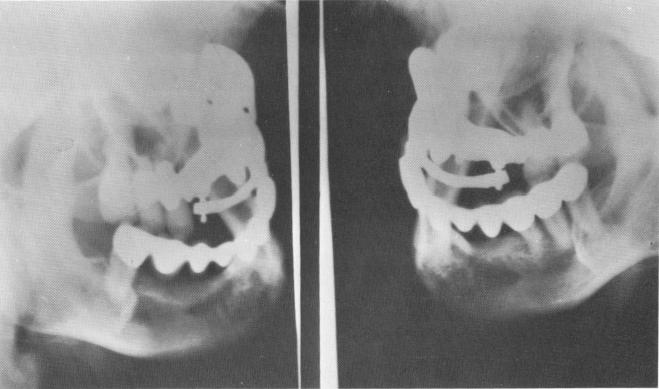

Fig. 15-21. Two lateral plate views.

2 Lateral plate views of maxillary anterior ridge implant, template, bar